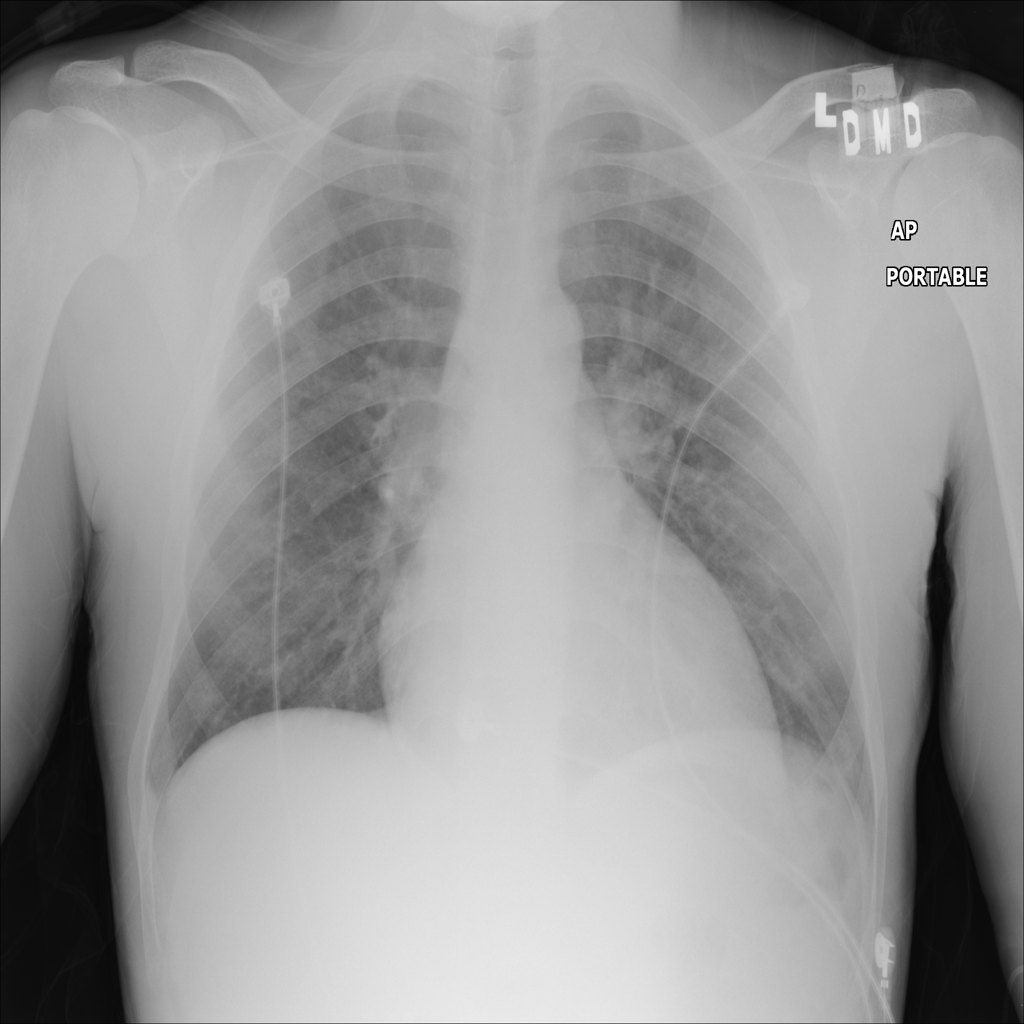

PAT-E828 · IMG-004Edema

PAT-E828 · IMG-004

AP